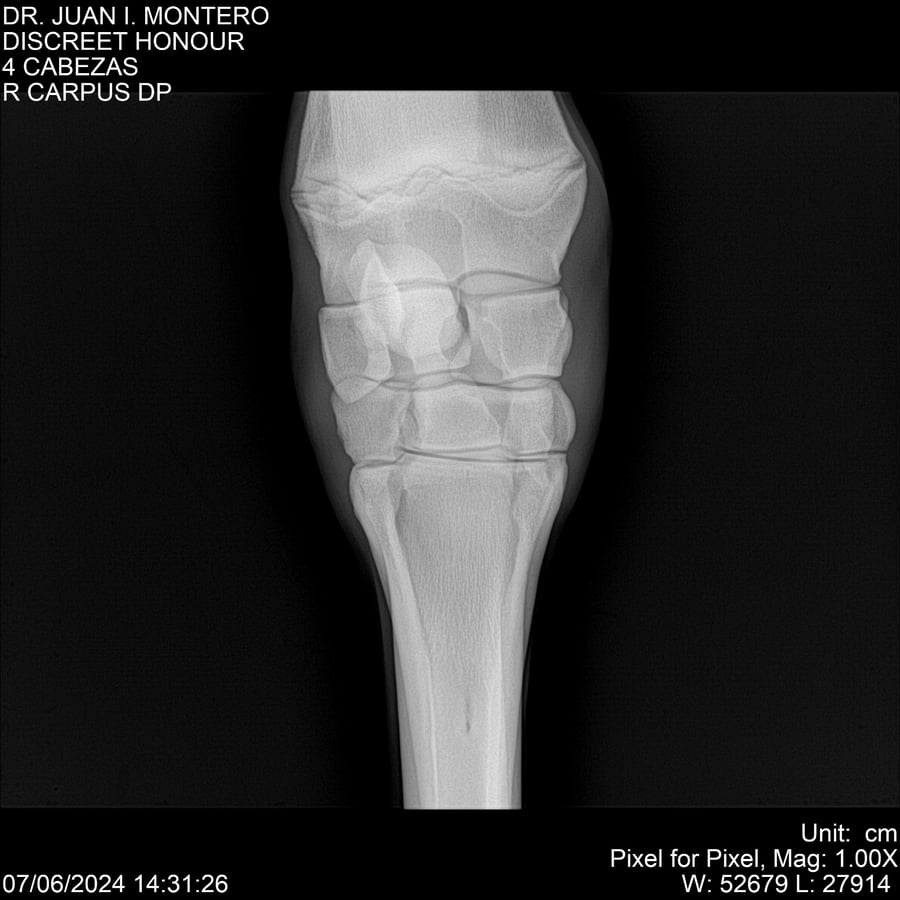

LOTE 6, DISCREET HONOUR 🔥 🔥 🔥 Lote Anterior Volver al remate Lote Siguiente Ficha Contacto Montevideo - Ficha del Lote Identificador: #281093 Categoría: Yeguarizos Montevideo - 82 Visualizaciones ClicData Contacto Empresa: Abelenda N. R., Walter Hugo Nombre*: Teléfono* : E-mail* : Mensaje Enviar Registrese gratis Este contenido Exclusivo está disponible sólo para usuarios registrados Ingresar